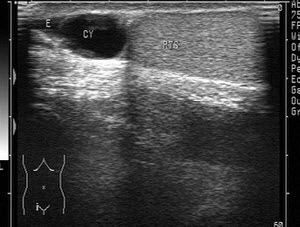

某患者右侧阴囊根部可触及小包块,超声声像图如下,最可能的诊断为()

A.精索鞘膜积液

B.睾丸鞘膜积液

C.附睾囊肿

D.睾丸肿瘤

E.附睾血肿